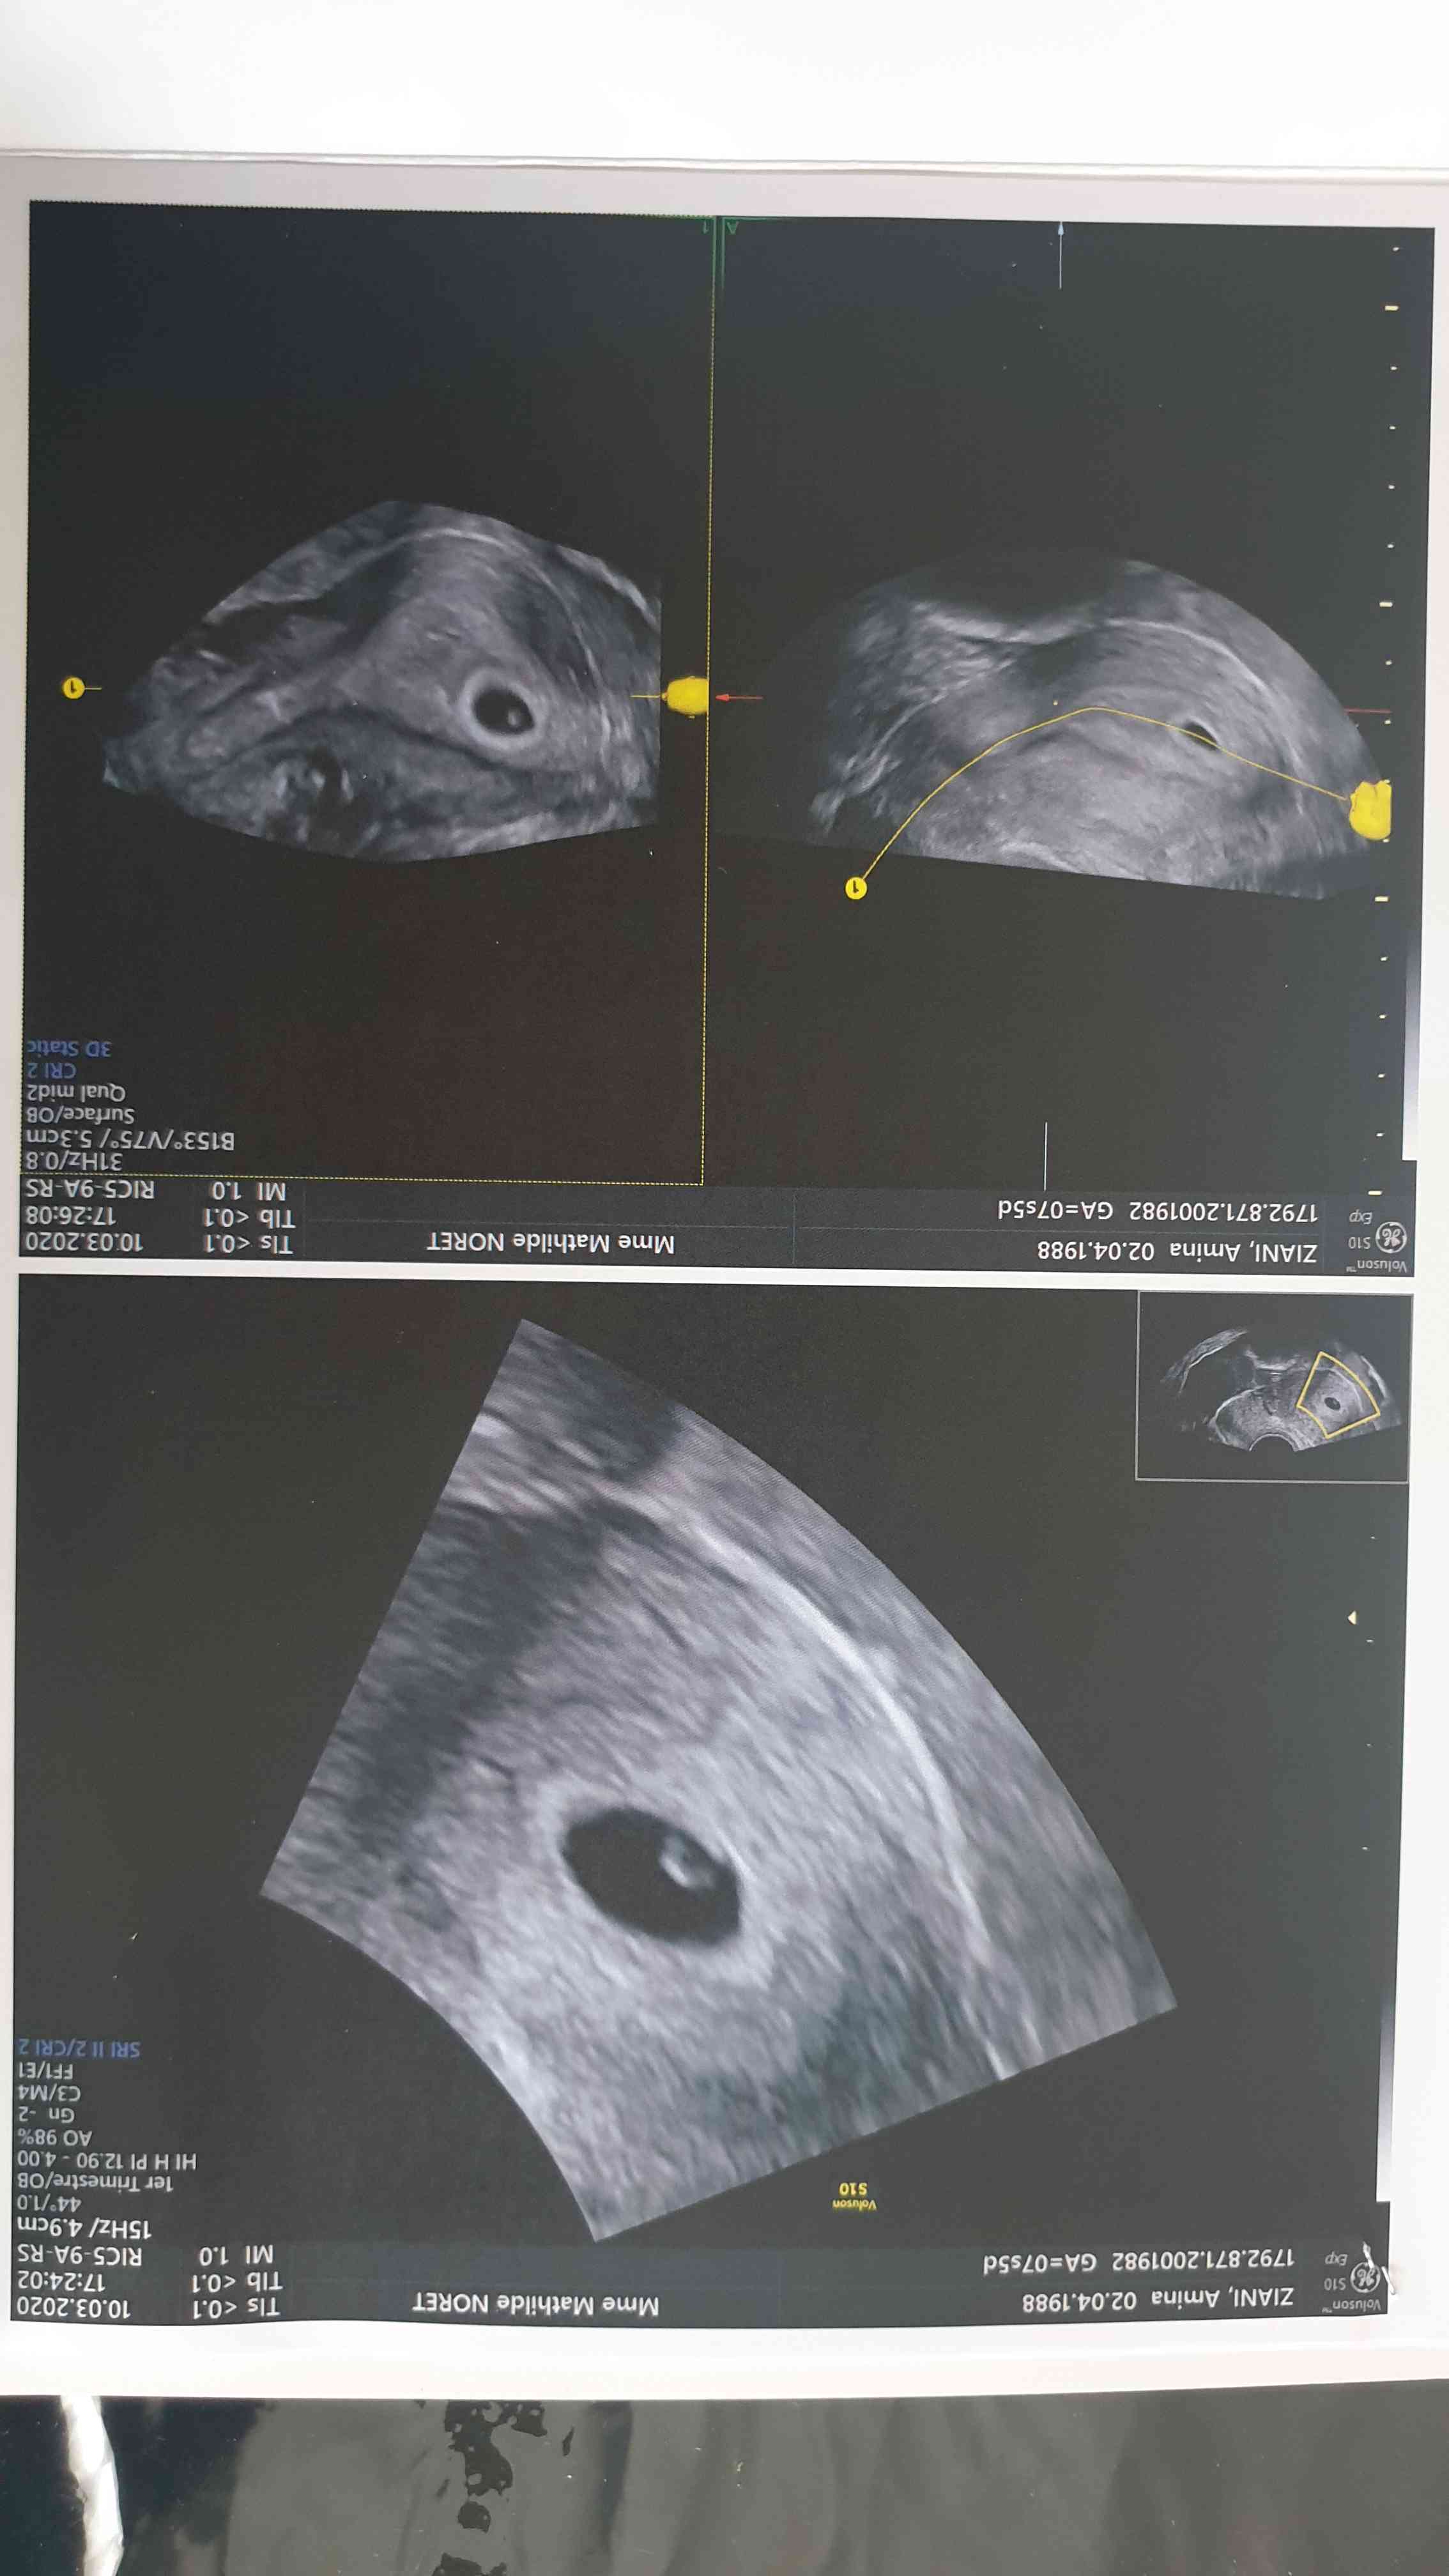

انا حامل و اخرموعد الدورة كان 16\01\2020 لما عملت ايكو قالت لي الدكتورة حملك سار يوم 19\02 و حجم الجنين 1.82ملم يعني صغير جدا هل حملي جيد ام في خطر

الملفات المرفقة:

71dddc23-df95-41ab-9cd1-eca5ac87241d